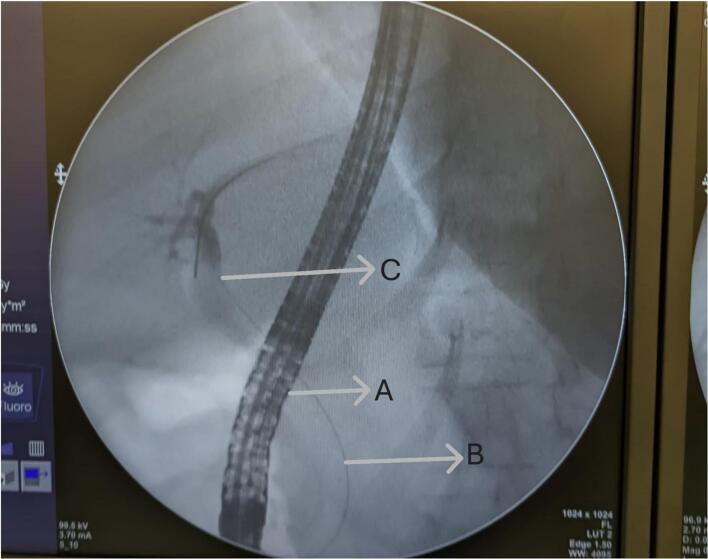

We present a case of a 30-year-old pregnant at 18 weeks of gestation who presented with acute-onset, progressively worsening epigastric pain radiating to the back associated with nausea and bilious vomiting but no fever. Laboratory investigations revealed elevated serum amylase and lipase, consistent with acute biliary pancreatitis, alongside obstructive biochemical features on liver function tests. Imaging confirmed multiple gallstones, choledocholithiasis, and a dilated common bile duct (CBD). She underwent successful ERCP with sphincterotomy and stone extraction followed by laparoscopic cholecystectomy in the same session. The patient had an uneventful recovery and was discharged on postoperative day three without complications.

The second trimester is considered the safest period for surgical intervention, given the lower risk of fetal loss compared to the first trimester and reduced risk of preterm labor relative to the third trimester. ERCP is the gold standard for managing choledocholithiasis in pregnancy, with fluoroscopy-minimizing techniques employed to mitigate fetal radiation exposure. Laparoscopic cholecystectomy has demonstrated superior outcomes in terms of reduced postoperative morbidity, shorter hospital stays, and faster recovery compared to open surgery. This case underscores the importance of a multidisciplinary approach, incorporating gastroenterology, surgery, and obstetric expertise, to optimize outcomes in pregnant patients with biliary pancreatitis.

我们报告一例30岁妊娠18周的孕妇,其表现为急性发作、逐渐加重的上腹部疼痛,放射至背部,伴有恶心和胆汁性呕吐,但无发热。实验室检查显示血清淀粉酶和脂肪酶升高,符合急性胆源性胰腺炎,同时肝功能检查有梗阻性生化特征。影像学检查证实有多个胆结石、胆总管结石及胆总管扩张。她在同一次手术中成功接受了ERCP括约肌切开术和结石取出术,随后进行了腹腔镜胆囊切除术。患者恢复顺利,术后第三天出院,无并发症。

鉴于与孕早期相比胎儿丢失风险较低,且与孕晚期相比早产风险降低,孕中期被认为是手术干预的最安全时期。ERCP是妊娠期处理胆总管结石的金标准,采用使荧光透视最小化的技术以减轻胎儿辐射暴露。与开放手术相比,腹腔镜胆囊切除术在降低术后发病率、缩短住院时间和更快恢复方面已显示出更好的效果。该病例强调了多学科方法的重要性,包括胃肠病学、外科和产科专业知识,以优化妊娠期胆源性胰腺炎患者的治疗效果。